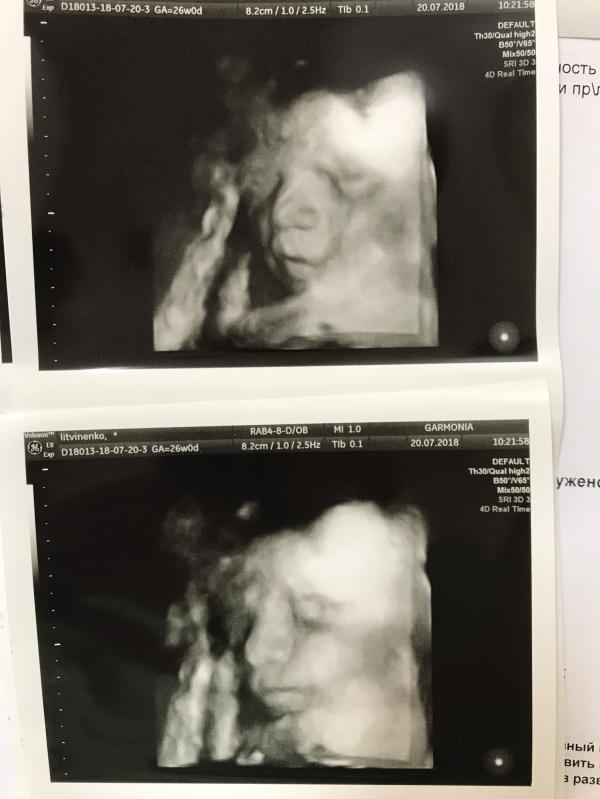

Что-то я давно не писала про беременность, надо исправиться. А то самой потом будет интересно вспомнить 😄

Сходила я на УЗИ между скринингами, на всякий случай. Было 26 недель и всё на отлично. Всегда утешаю себя тем, что хоть мне даётся тяжело беременность, обитатели пуза чувствуют себя прекрасно 😄 Подтвердили девочку 😊

Изжога пока редкий гость, а вот боль справа под рёбрами бывает очень выматывающей. И симфизит напоминает о себе жгучими ощущениями в известном месте, в остальном, жить можно 😅